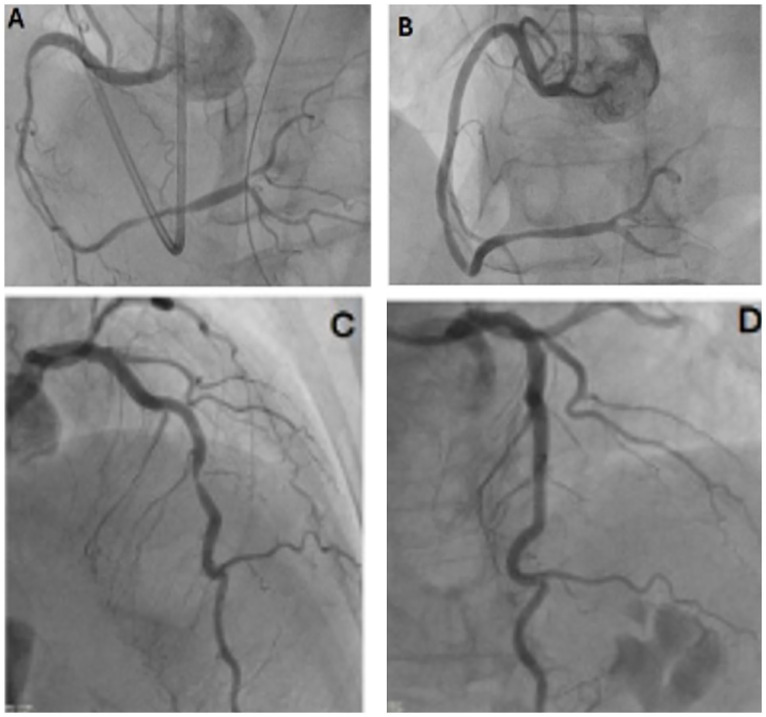

Refractory coronary artery spasm is a challenging condition with many complications, including acute myocardial infarction. We present the case of an elderly woman who developed refractory coronary artery vasospasm requiring extensive hemodynamic support. She had an abnormal electrocardiogram. She was diagnosed with severe coronary artery vasospasm that initially responded to intracoronary nitroglycerin. However, the course was complicated by arrhythmias and cardiogenic shock following an additional episode of vasospasm that required higher concentrations of nitroglycerin. Notably, this case is relatively less documented in women and within the South Bronx population. Refractory coronary artery spasm is a critical condition that can lead to life-threatening outcomes. Prompt and effective treatment is essential, especially for high-risk patients, to prevent cardiac ischemia. Given the significant dangers of delayed or insufficient treatment, it is crucial to manage coronary artery spasms proactively to enhance patient outcomes and avoid severe complications. In addition, this diagnosis should be strongly considered in women, with an emphasis on following guidelines for managing cases of acute myocardial infarction.